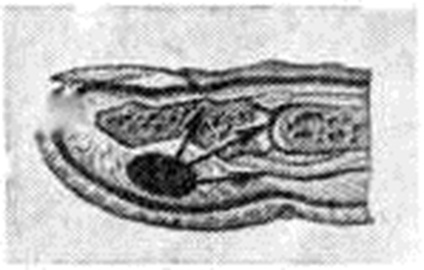

Подкожный Панариций— воспаление подкожной клетчатки пальца (рисунок 1, 4) — наиболее распространённая форма Панариций Чаще встречается подкожный Панариций ладонной поверхности дистальных фаланг. Так как на тыльной поверхности пальцев кожа подвижная, а подкожная клетчатка рыхлая и содержит много лимфатических, сосудов, широко анастомозирующих с лимфатических, сосудами ладонной поверхности, то при расположении гнойного очага на ладонной поверхности пальца отёк, припухлость и гиперемия кожи более чётко выражены на боковых поверхностях и тыле пальца. Палец (или фаланга) увеличивается в объёме, становится напряжённым (цветной рисунок 2, 3). Большая толщина, плотность и неподатливость кожи ладонной поверхности, ячеистое расположение подкожной клетчатки способствуют быстрому распространению воспалительного процесса в сторону надкостницы и сухожилий. Боль постоянная, усиливается при разгибании и ослабевает при умеренном сгибании пальца. Точка наибольшей болезненности соответствует локализации центра гнойного очага. Часто больной лишается сна из-за боли, изнурён, температура тела повышается до 38—39°. В гнойное воспаление могут вовлекаться кость, сухожилия, суставы (рисунок 2). Из очага, локализующегося в проксимальной фаланге пальца, гнойный процесс может перейти по рыхлой клетчатке межпальцевых промежутков в каналы червеобразных мышц, дистальный отдел ладони и на проксимальные фаланги соседних пальцев (рисунок 3).